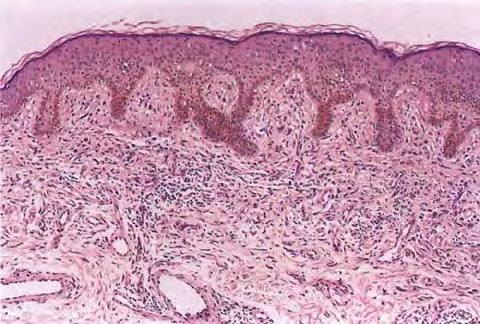

mastocytose